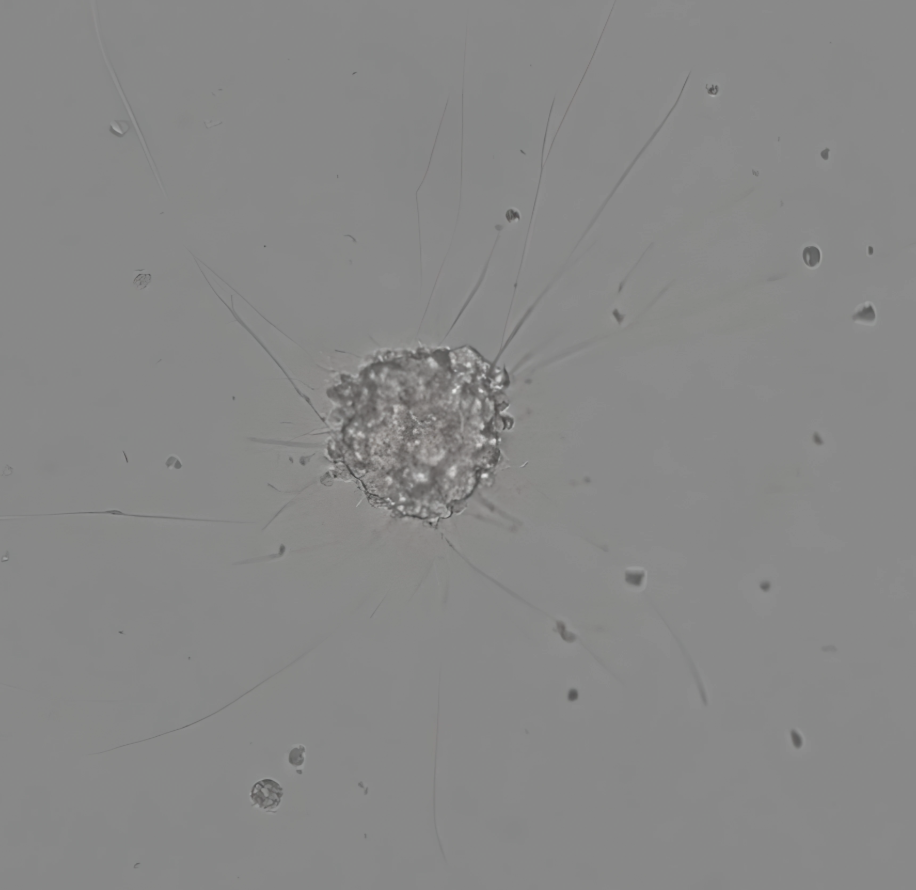

This project uses advanced 3D tumour models to test combinations of ALK-blocking drugs with ATR inhibitors to see which are most effective against chemotherapy-resistant tumours.

A tumour spheroid